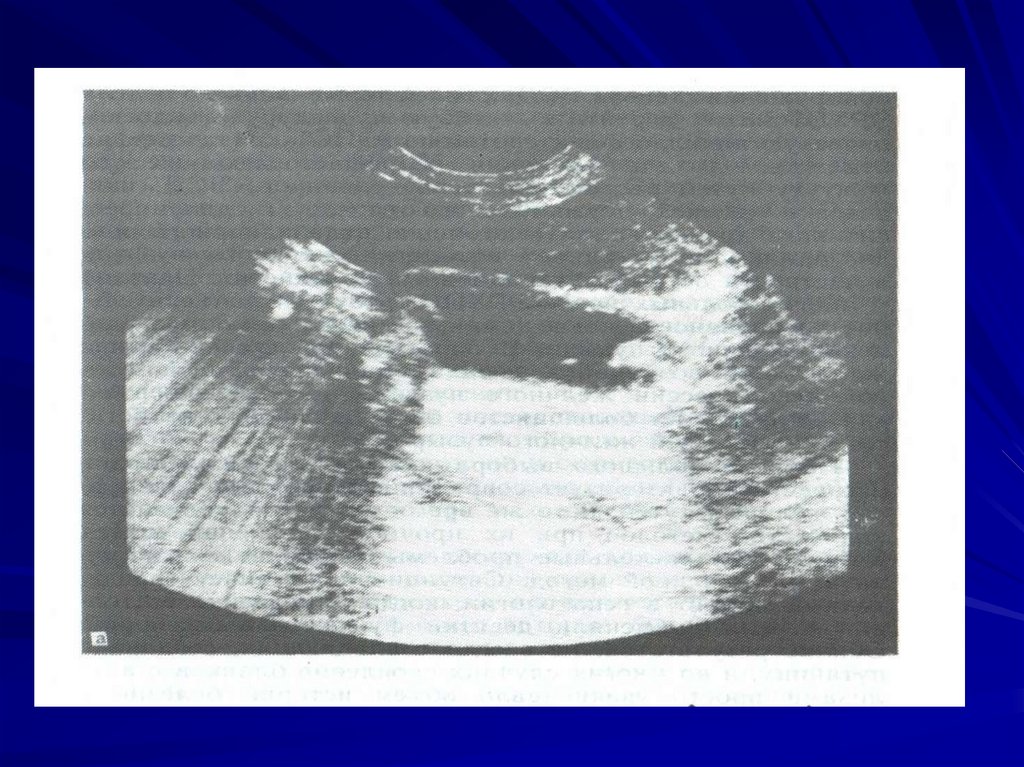

Обнаружение симптома эхонегативной

полосы (ободка) различной формы и

ширины, прилегающего к желчному пузырю,

может свидетельствовать о формировании

перивезикального абсцесса. Чаще всего при

остром холецистите в полости пузыря

лоцируются конкременты: гиперэхогенные

структуры, дающие эхо-тень. Выявление

фиксированной эхоструктуры с

акустической тенью в области шейки

желчного пузыря - признак вколоченного

камня.

Дополнительным симптомом острого

холецистита служит положительный УЗипризнак Мерфи - усиление боли в зоне

желчного пузыря на вдохе под УЗИдатчиком. При оценке результатов УЗИ

обращают внимание на состояние

внепеченочных желчных протоков: в норме

ширина гепатиколедоха не превышает 8 мм.

Увеличение диаметра гепатиколедоха до 9

мм и более может указывать на желчную

гипертензию, обусловленную камнем или

стриктурой.